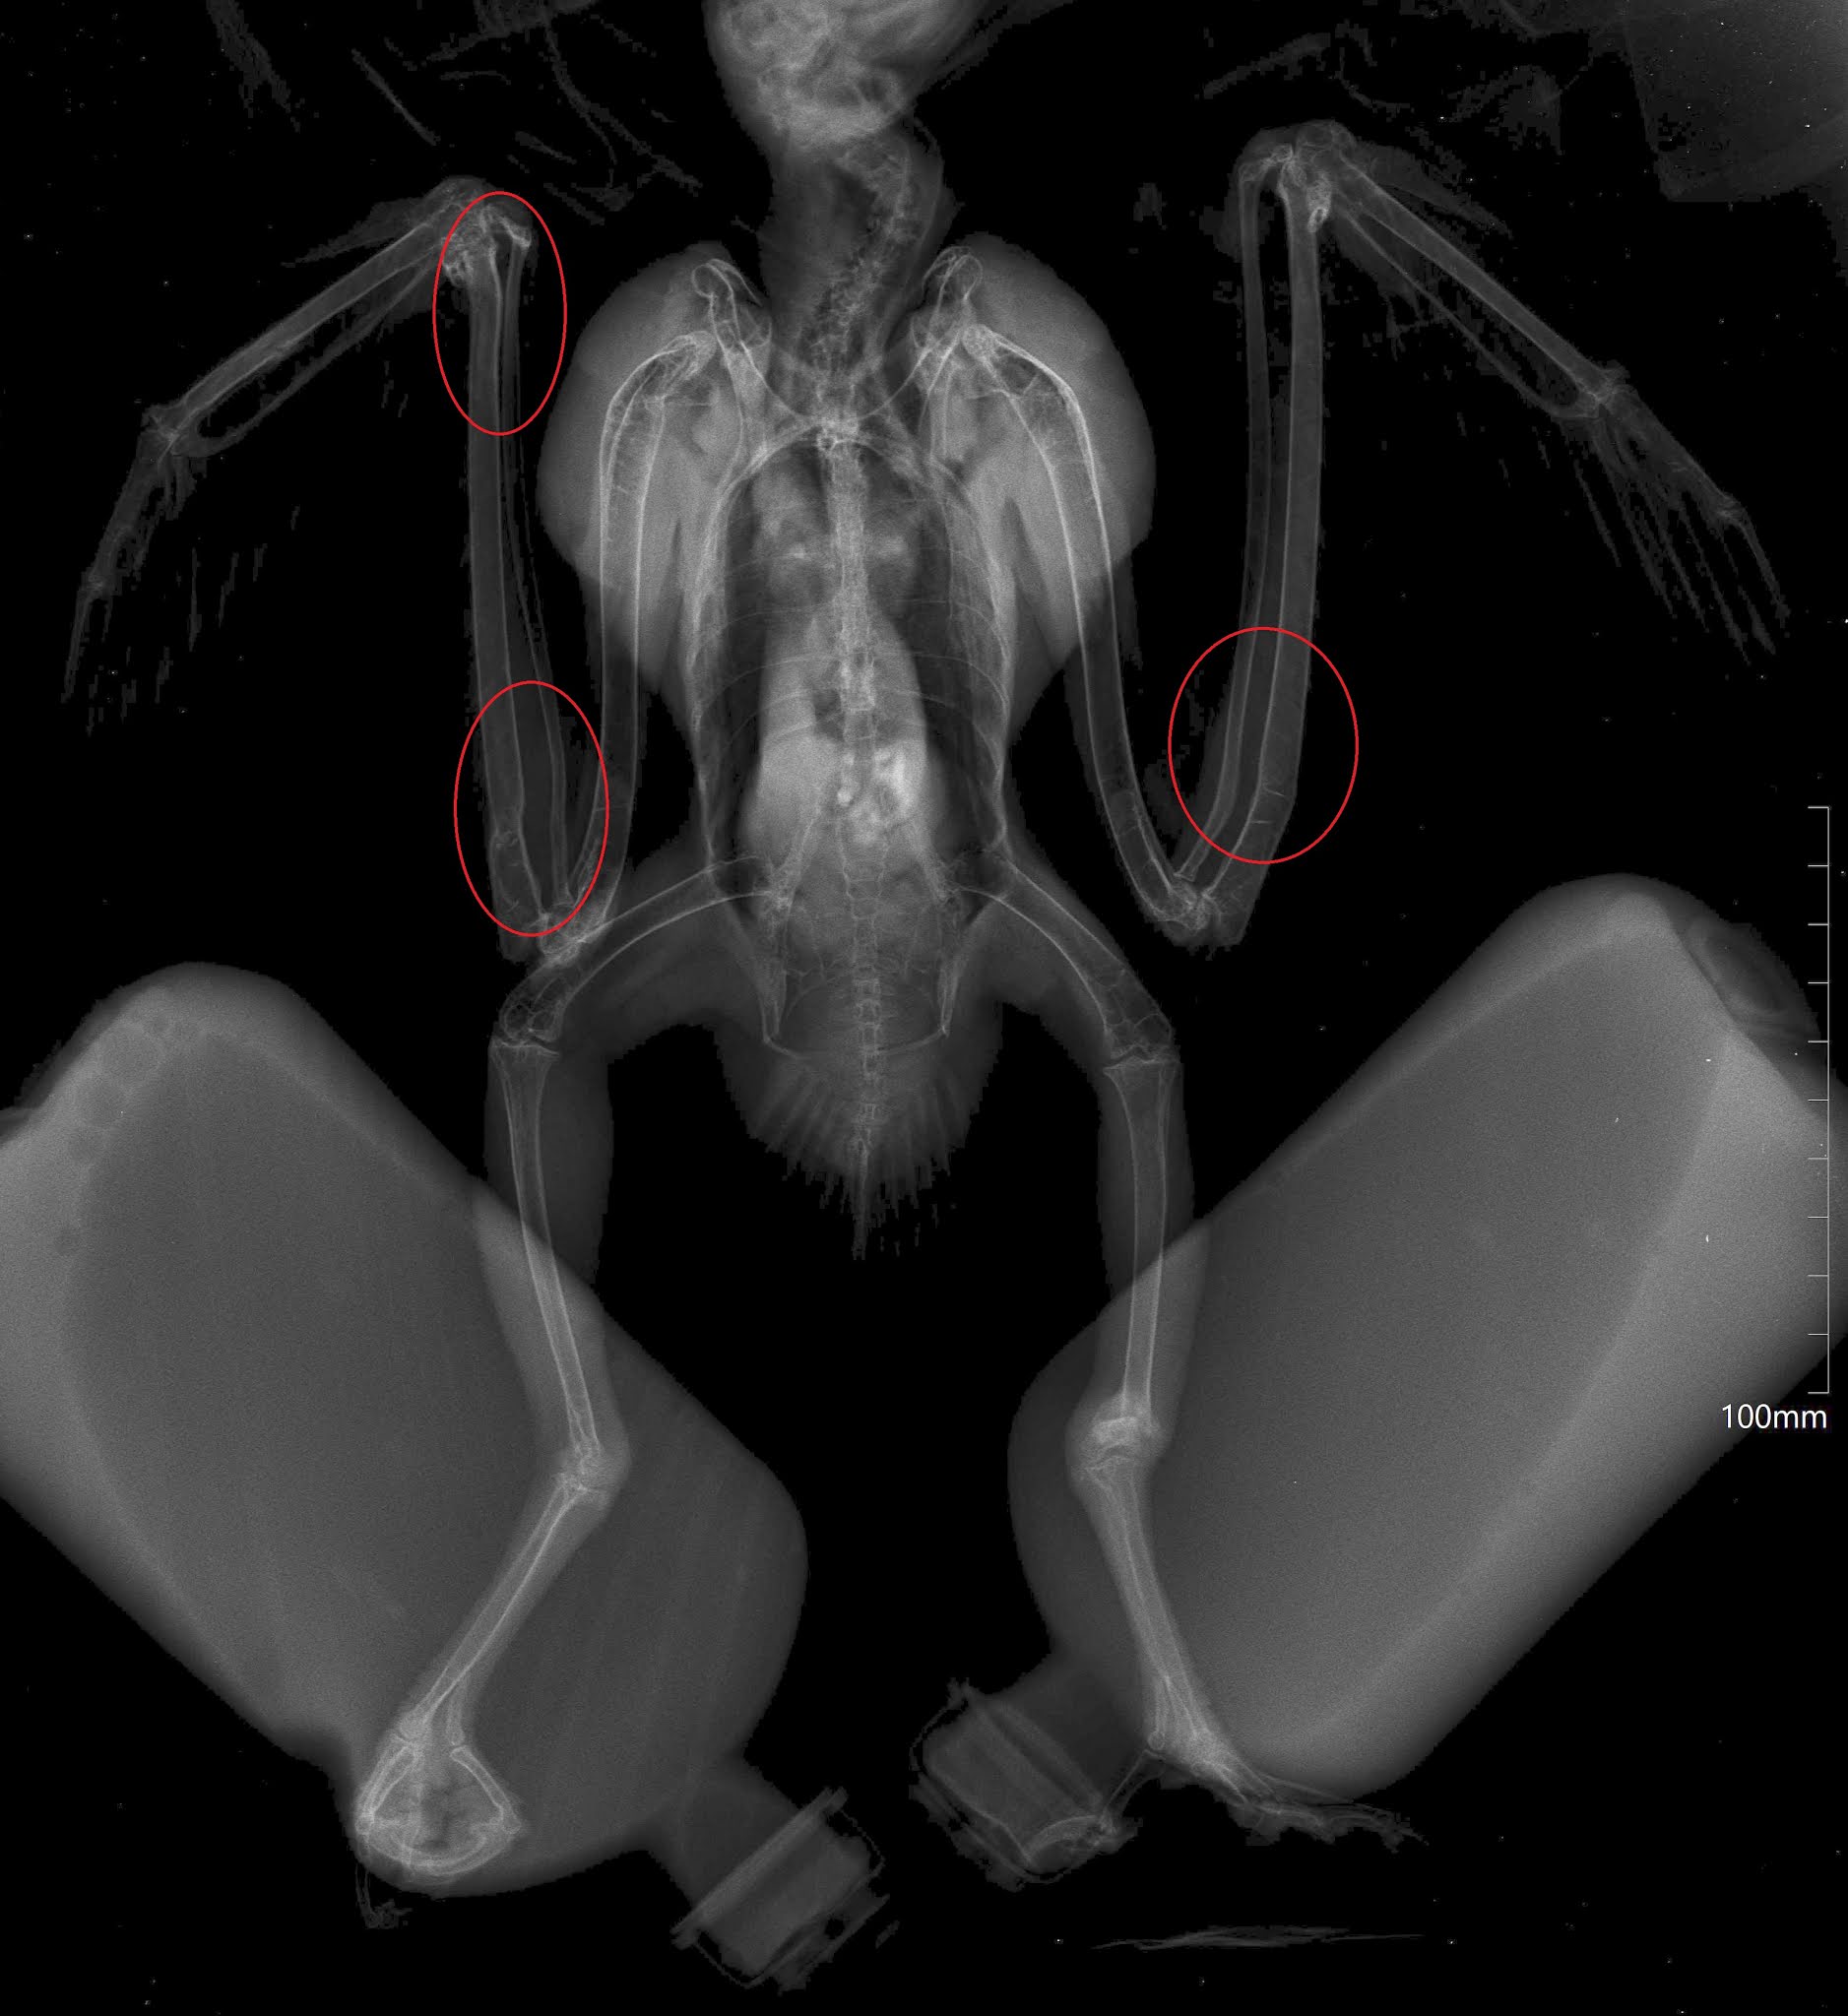

O Raio-x realizado mostrou graves deformidades nos ossos das asas e das patas, um sintoma compatível com osteodistrofia nutricional (patologia muito frequente em animais mantidos com alimentação inadequada durante o seu crescimento, e/ou por um longo período de tempo).

Infelizmente, não é possível corrigir estas alterações ósseas, mas, apesar do esforço evidente que faz, o animal está atualmente a voar.